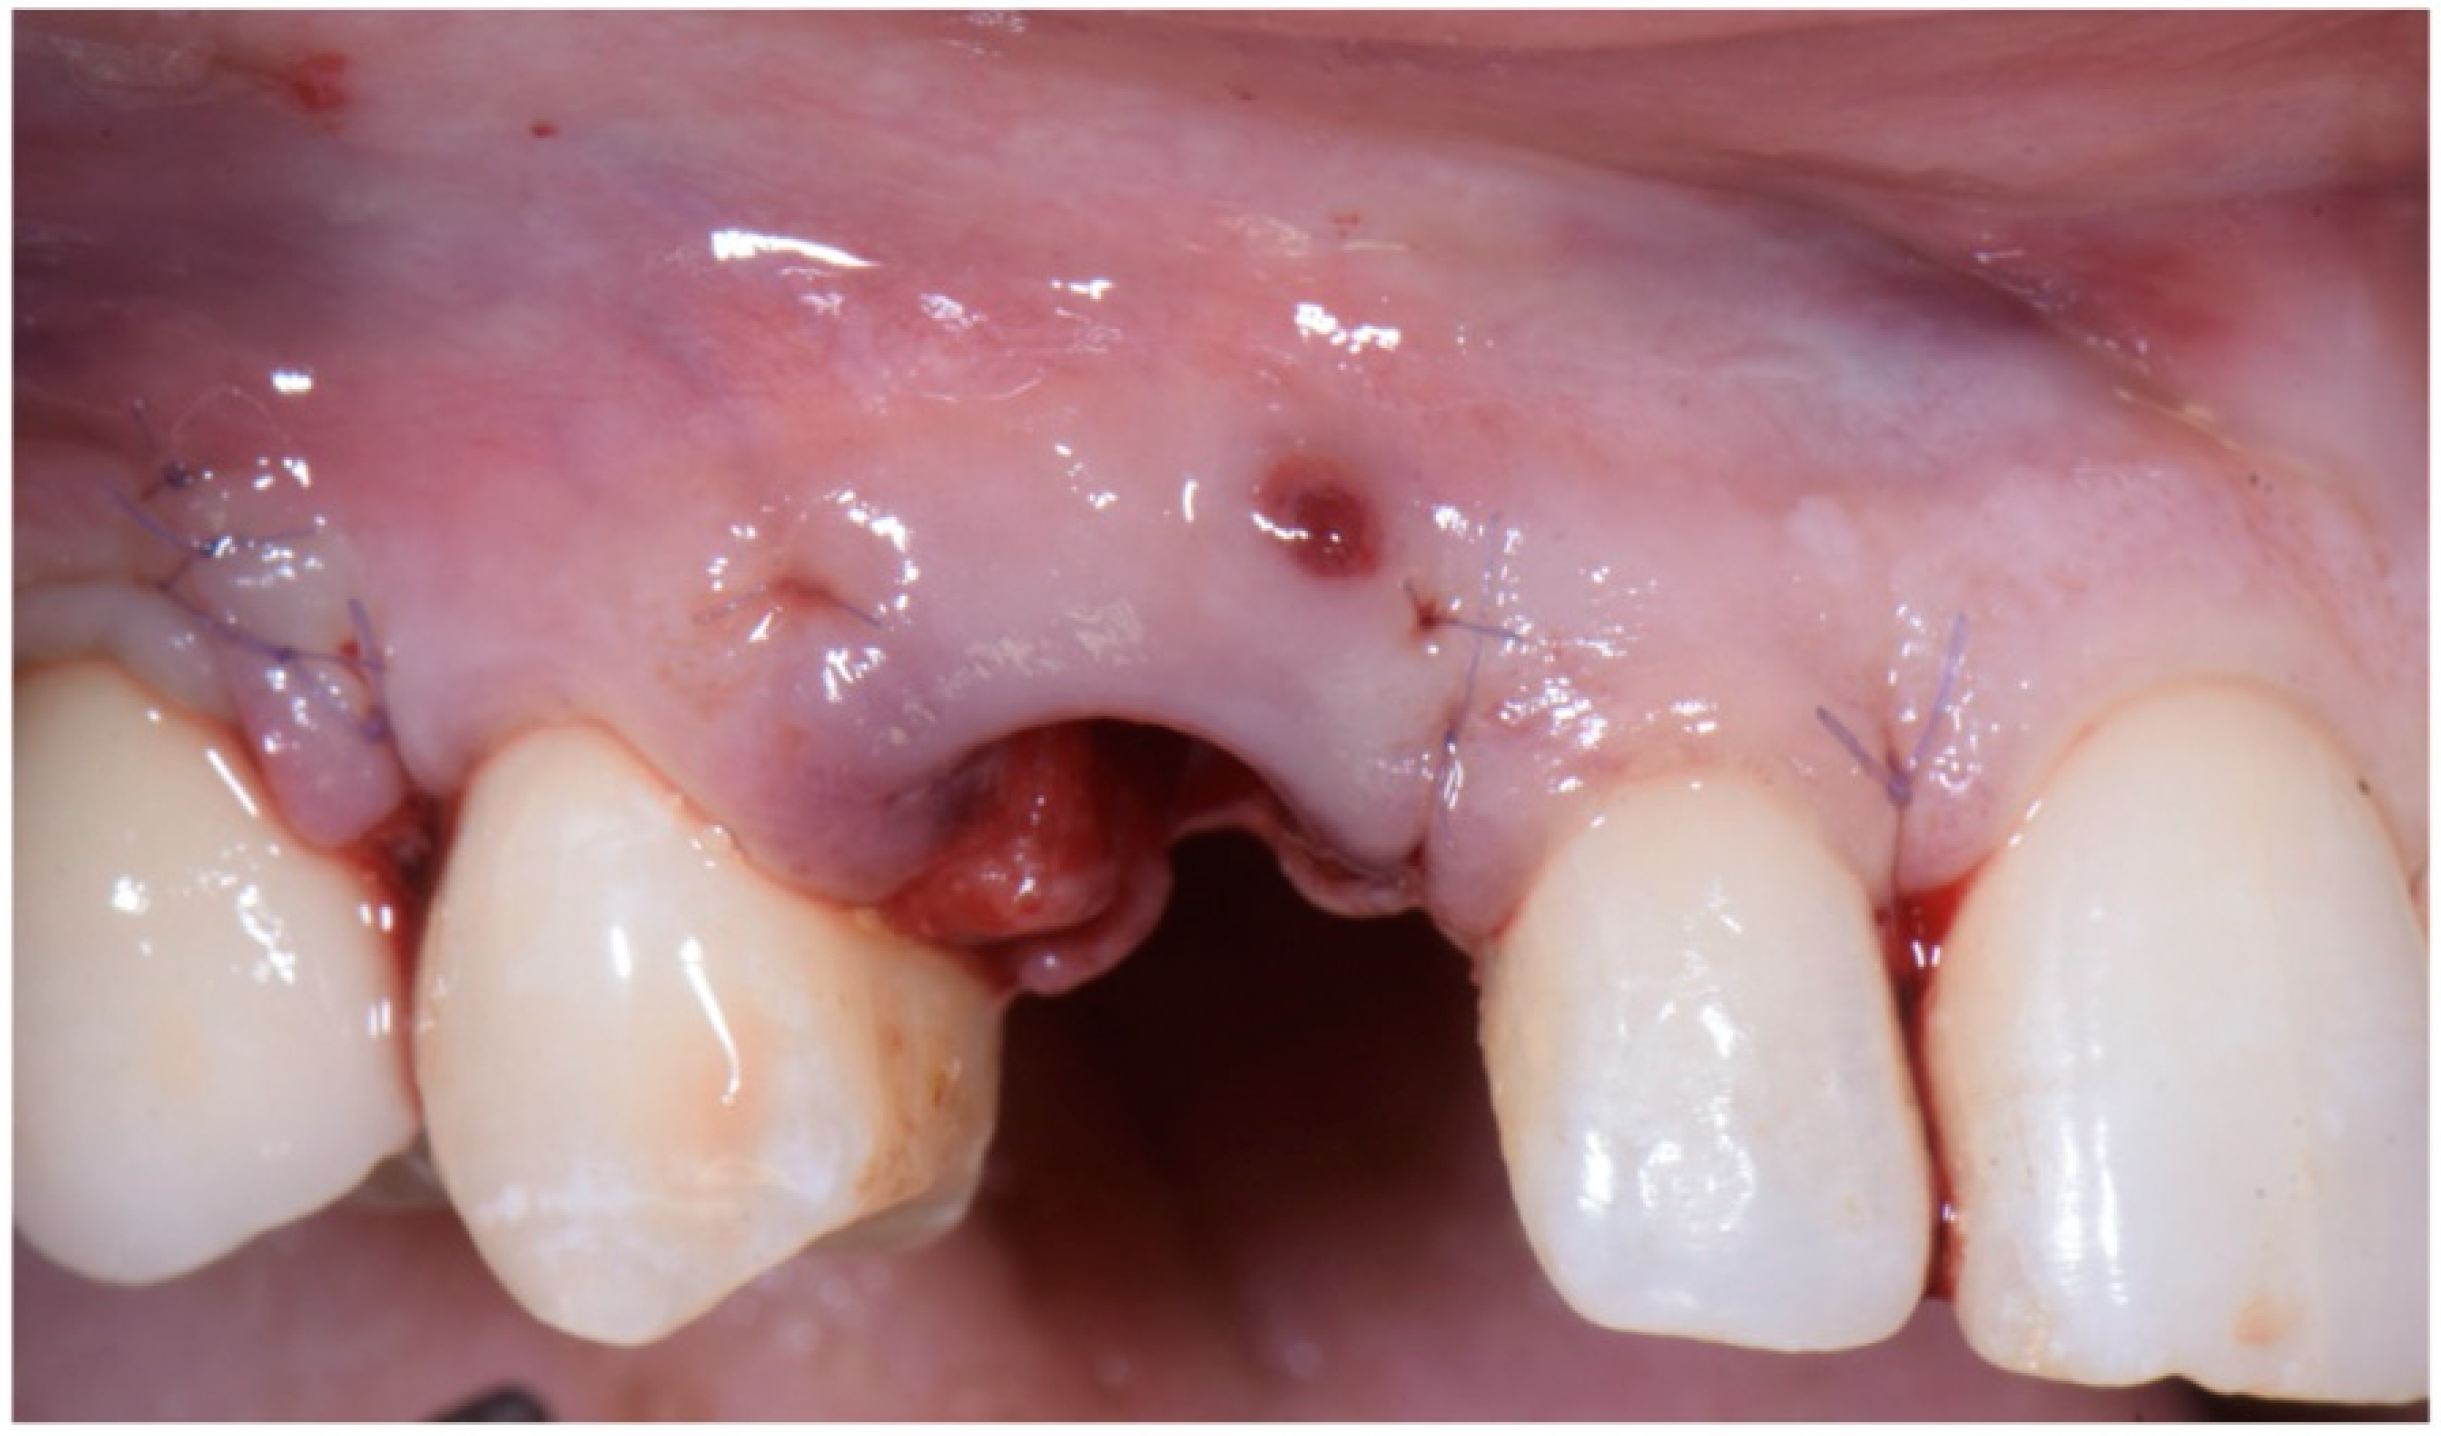

The closure of the surgical papilla over the anatomical papilla was performed with simple interrupted sutures (7/0 thread; 8 mm needle). First, we sutured the weakest papilla (in this case, the mesial one) before placing the provisional crown (Figure 10); this simplified suturing and made it possible to obtain an ideal adaptation of the surgical papilla on top of the smaller anatomical papilla. After screwing the provisional, it was time to suture the second surgical papilla (the distal one) onto the larger anatomical papilla with another simple interrupted suture (Figure 11a,b).

Figure 4. (a,b) Lateral-approach coronally advanced envelope flap, with oblique submarginal interproximal incisions directed towards the flap’s center of rotation (the tooth to be extracted).

Figure 11. (a,b) Suture of the second surgical papilla (the distal one) onto the larger anatomical papilla with a simple interrupted suture, after screwing the provisional.